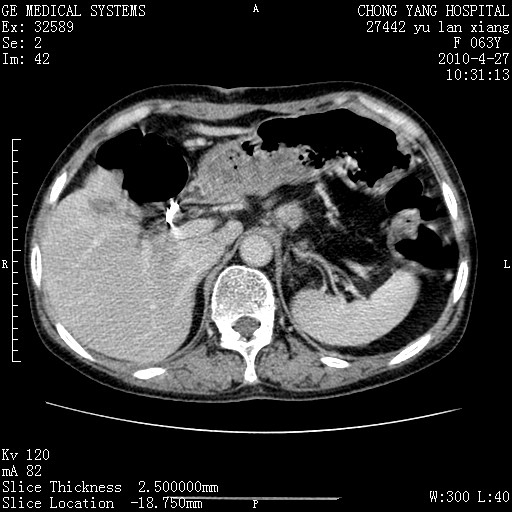

标题: CT26066:F63Y 上腹正中压痛半月,CA199:7400u/ml,MR示胰腺炎伴 [打印本页]

胰腺癌侵犯腹腔动脉干-分支、胃壁、左侧膈肌伴胰周及腹膜后淋巴结转移、胆囊切除术后。

胰腺癌侵犯腹腔动脉干-分支、胃壁、左侧膈肌伴胰周及腹膜后淋巴结转移、胆囊未显影。